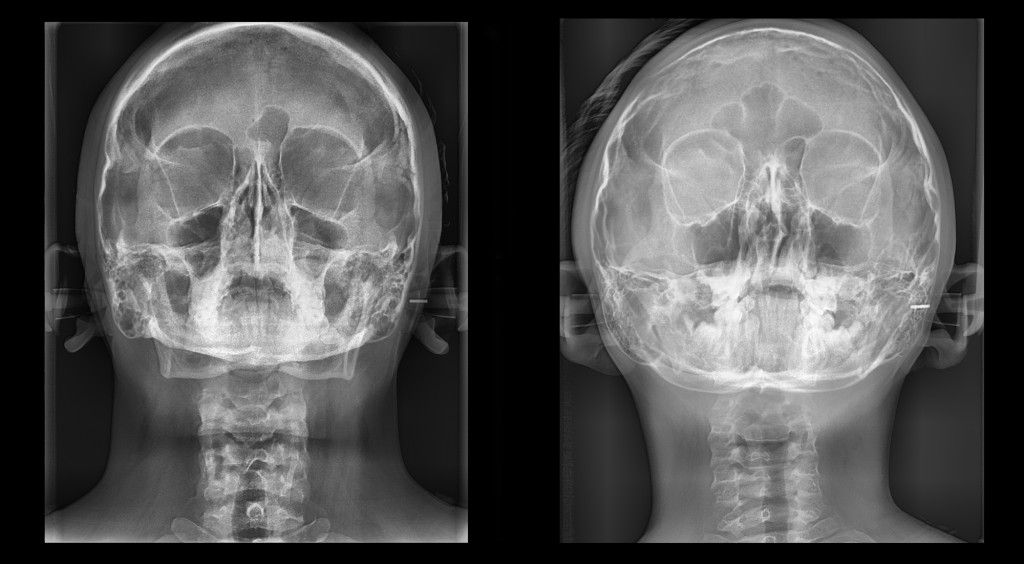

WATERS

Lupa anatómica que permite evaluar Patologías Sinusales, Fracturas Faciales, Evaluaciones del Piso Orbitario y Seno Maxilar